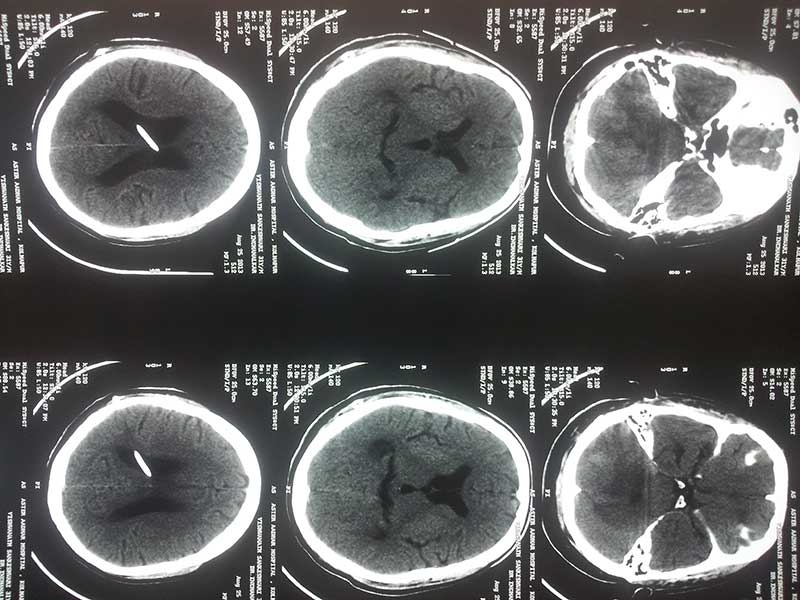

Pre OP CT

PRE OP CT 2